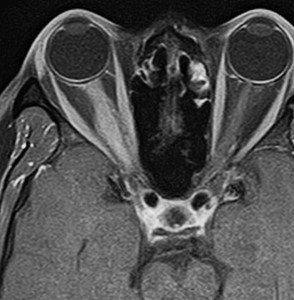

視神経鞘髄膜腫 optic sheath meningioma

眼窩内腫瘍です。視神経を包むし神経鞘から発生して,視神経鞘に沿って進展して増大します。視神経を圧迫してゆっくり症状が出ます。片目の視力が落ちるというのが症状ですが気づかれず発見が遅れることが多いでしょう。眼底検査で,初期には視神経乳頭 optic discの腫れが見られ,視力が悪化していくと視神経萎縮となります。眼底検査で動静脈シャントが見られるのも特徴的で,視力低下と視神経萎縮と併せてHoyt-Spencer triadと言われました。視力がほぼ消失するまで腫瘍が増大すると,眼球が前に押されて,眼球突出 exophhalmus, enophthalmus という症状が出ます。

治療は手術摘出ですが,この腫瘍を摘出するとほぼ確実に片眼の視力を消失します。ですから視力が無くなるまで手術は待機するという考え方が一般的です。数年以上視力があまり低下しないで腫瘍も増大せず経過する患者さんもいます。視力温存目的で治療するなら,視力の良いうちに定位放射線治療を行うべき疾患です。だからといって何でも定位放射線治療をすればよいというものではありません。問題は,視神経管から鞍結節に腫瘍が伸展している例があるということです。ここを放置すると反対側の健常な眼の視力が侵されることになりかねないので慎重に判断します。

放射線治療をした例

鞍結節部から視神経管を伝わり視神経鞘に伸びていた例です。鞍結節部と視神経管での視神経圧迫があったのでそこを除圧するために摘出したのですが,グレード2の髄膜腫で再発しました。下のMRIは,放射線治療 50Gy/25frしてから5年後の画像です。腫瘍は大きくなっていませんし,右の視力はVd 0.5あり,有用視力といえるほどの視野ではありませんが,視野は上の方で残っています。